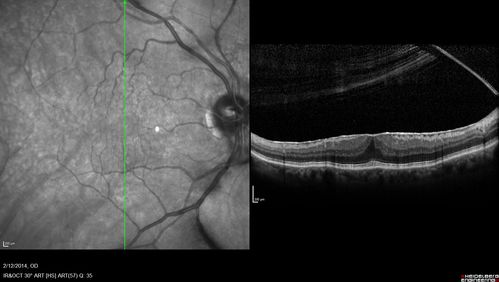

Vitreomacular Traction -> Macular Hole -> Aborted Macular hole

Progression of VMT in both eyes over time